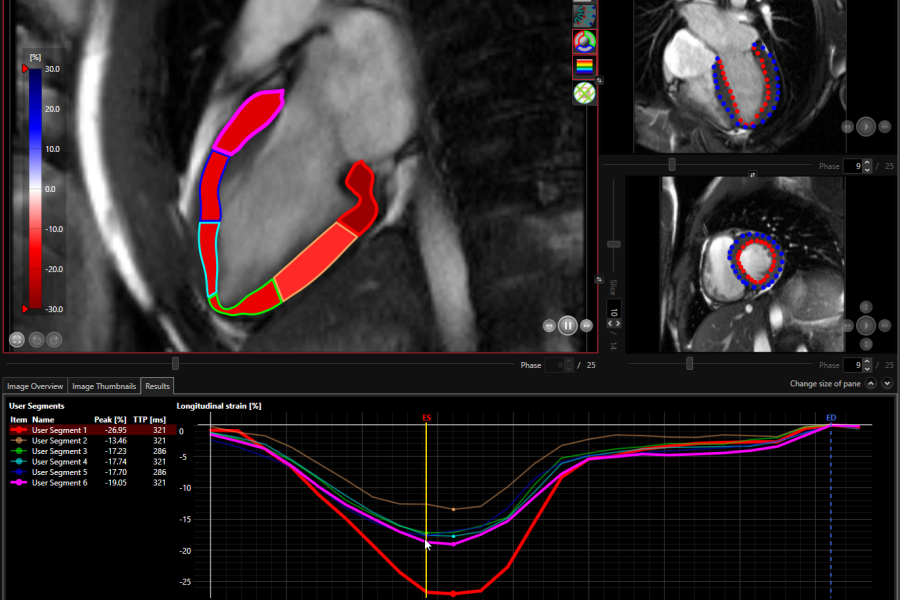

• User segment model with up to 20 segments per slice

• Three strain types are determined: longitudinal, circumferential, and radial;